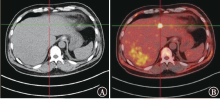

原发性心脏血管肉瘤是一种来源于血管内皮的恶性肿瘤,极为罕见且预后极差,病理诊断特异性及敏感性较高的标志物是CD31和CD34,手术不能根治性切除,姑息放疗、系统化疗和抗血管生成靶向治疗可延长患者生存期。现报道1例心脏原发血管肉瘤患者的诊疗经过,并就相关文献进行复习,以提高对该类疾病的认识。